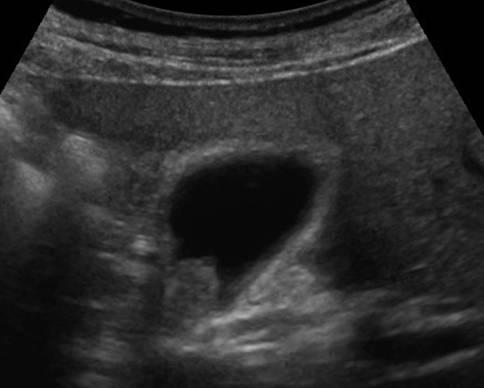

Ung thư túi mật

» Thông tin: Nam giới – 75 tuổi.

» Lâm sàng: Đau mạn sườn phải.